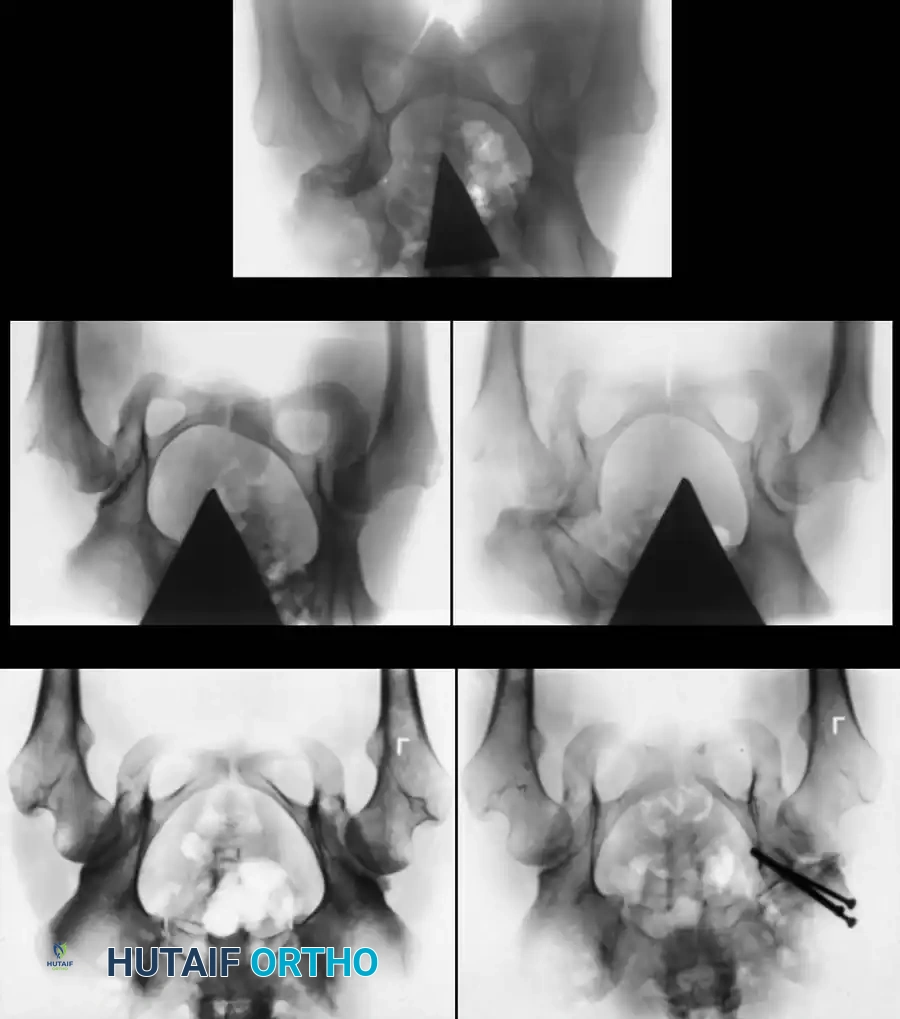

Radiography: Becomes reliable after 4 to 6 months as the ossific nucleus of the femoral head appears. Key radiographic parameters include:

* Hilgenreiner's Line: A horizontal line through the triradiate cartilages.

* Perkins' Line: A vertical line dropped from the lateral margin of the acetabulum, perpendicular to Hilgenreiner's line.

* Shenton's Line: A continuous arc drawn from the medial border of the femoral neck to the superior border of the obturator foramen. Disruption indicates proximal migration.

* Acetabular Index: The angle between Hilgenreiner's line and a line drawn from the triradiate cartilage to the lateral edge of the acetabulum. Normal is <30 degrees in newborns; >35 degrees is highly suspicious for dysplasia.

Radiographic evaluation: Normal hip anatomy (left) versus Dysplastic hip anatomy (right) demonstrating disruption of Shenton's line and an increased acetabular index.

Radiographic appearance following a complex pelvic osteotomy with internal fixation, demonstrating improved center-edge angle and acetabular coverage.